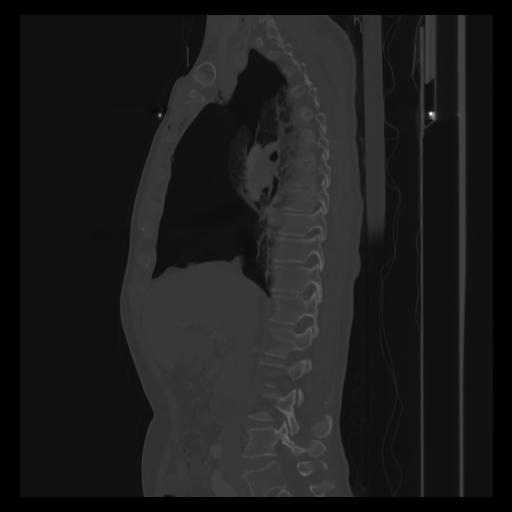

30 CUERPO,CE,Sagittal,3.000,CUERPO,Sagittal,